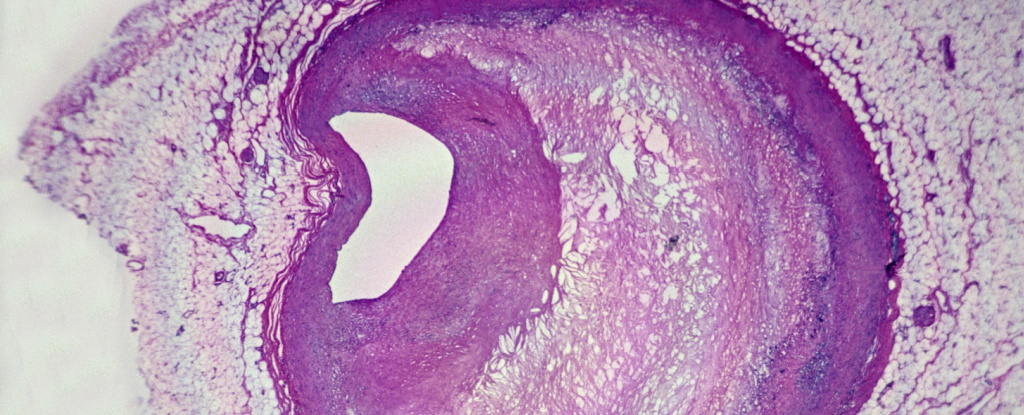

So to clarify for those who don’t want to read the article and a few supporting pieces, this is talking about the presence of plastic micro particles in plaques removed from patients.

Removing the plaque can reduce the risk of stroke so it is done fairly frequently. When they took out the plaque they checked for polyethylene, common plastic for bottles, plastic containers, and similar uses, and for PVC, famous for pipes and incredibly sweaty pants.

In both cases microplastics were found in the plaque. Both of these plastics have been shown to cause inflammation in other experiments where the plastic is introduced into the body.

What they seem to be suggesting is that some amount of the inflammation around a plaque could be caused or enhanced by these microplastics.

This study shows that in some plaques, about half of those examined, these two plastics were present. Previous studies have shown plastics can cause or enhance inflammation.

This study does not show that plastics are the primary cause of heart disease. It also does not show how much of an impact microplastics have on the formation of plaques, how dangerous they are, or whether they grow.